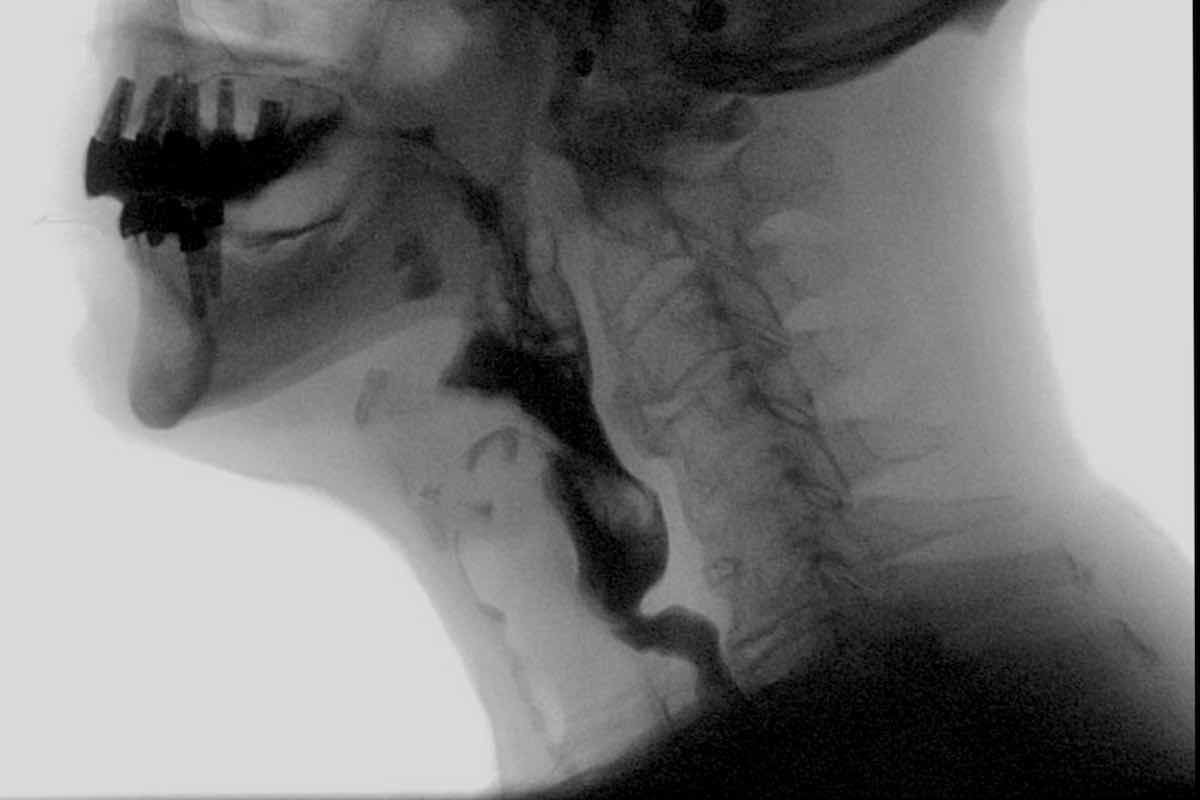

Dysphagia and modified barium swallow study